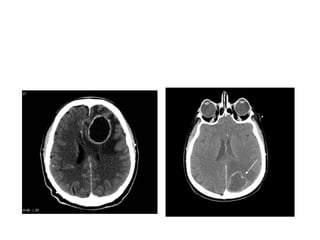

Computed tomographic (CT) scan with

Computed tomographic scan

Early cerebritis appears as an irregular area of low

density that does not enhance following contrast

injection.

As cerebritis evolves, the lesion enlarges with thick

diffuse ring enhancement following contrast injection.

The ring of contrast enhancement represents

breakdown of the blood-brain barrier and the